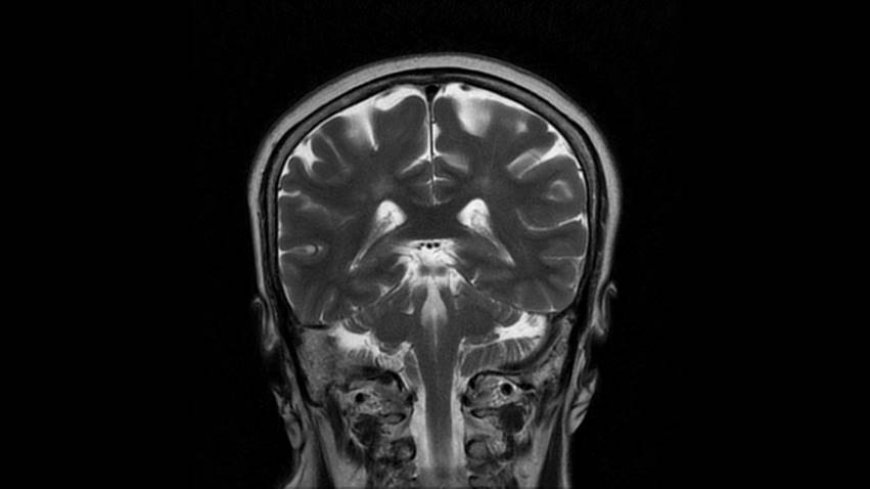

MRI of Brain

Coronal T2